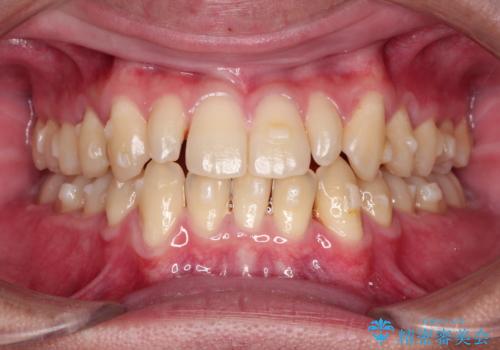

- 当院で矯正治療を行っており、上の前から2番目の歯の形も気になるので治したいと希望がありました。

矮小歯といわれる通常よりも小さい歯であったので、こちらにオールセラミッククラウンを装着して自然な歯の形にすることにしました。